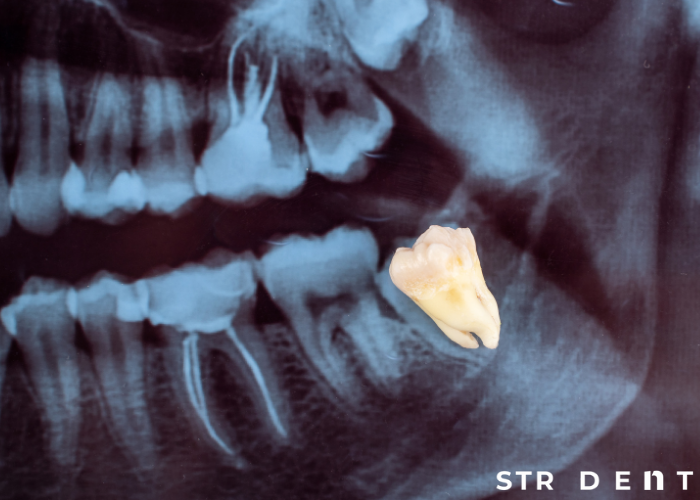

Yirmilik diş çekimi, yaygın bir cerrahi işlemdir ve çekim sonrası yan etkiler sıkça görülebilir. Bu yan etkilerden biri de yanakta morarma veya yeşillenmedir. Bu durum, genellikle endişe verici olmasa da hastaların bilgilendirilmesi ve gerektiğinde müdahale edilmesi önemlidir.

Yirmilik diş çekimi sırasında çevre dokulara yapılan cerrahi müdahale, kan damarlarının zarar görmesine neden olabilir. Bu durumda kan, dokulara sızar ve cilt altında birikir. Başlangıçta morluk olarak kendini gösteren bu durum, iyileşme sürecinde yeşil renge dönüşebilir. Bu yeşillenme, kanın vücut tarafından emilmesi sırasında ortaya çıkan biliverdin maddesinden kaynaklanır. Biliverdin, hemoglobinin parçalanmasıyla oluşur ve cilt altında yeşilimsi bir renk değişikliği oluşturur.